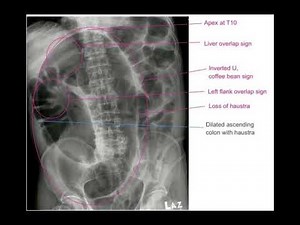

X-ray Coffee Bean Sign - Sigmoid Volvulus

Radiology - Sigmoid Volvulus

X-ray - Sigmoid Volvulus

On XR - Sigmoid Volvulus

Volvulus Radiograph - Sigmoid Volvulus